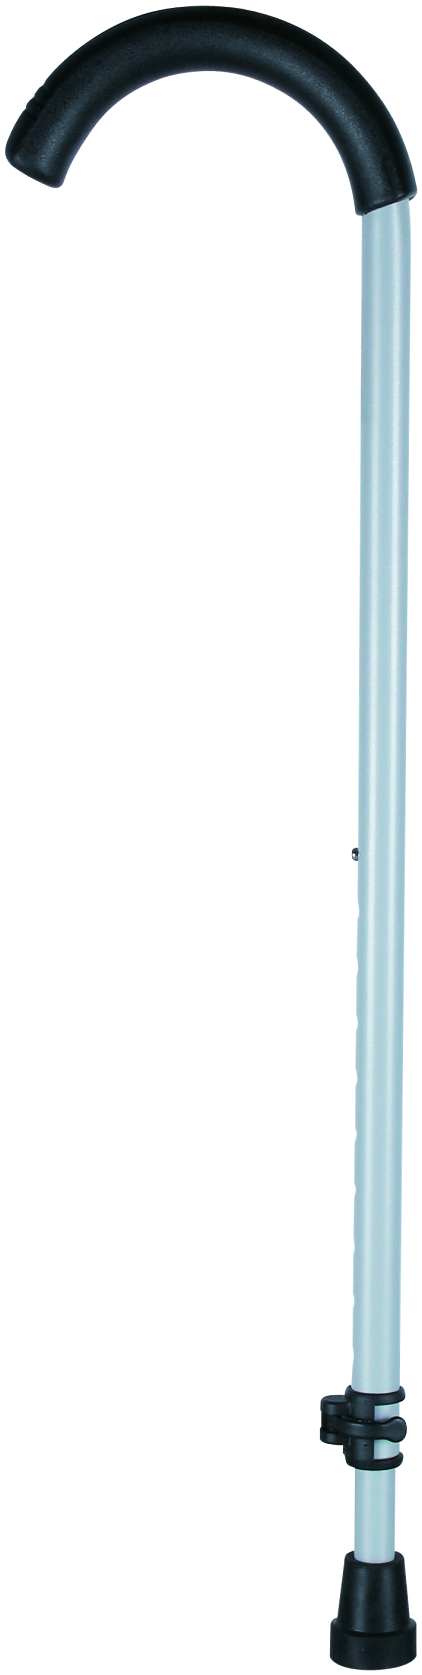

- Crutches

Crutches are an important medical rehabilitation AIDS, branch cane, elbow crutches, axillary crutches, multi-foot crutches, crutches play an important role in walking, not only to provide support and balance, but also to help improve gait and reduce energy consumption